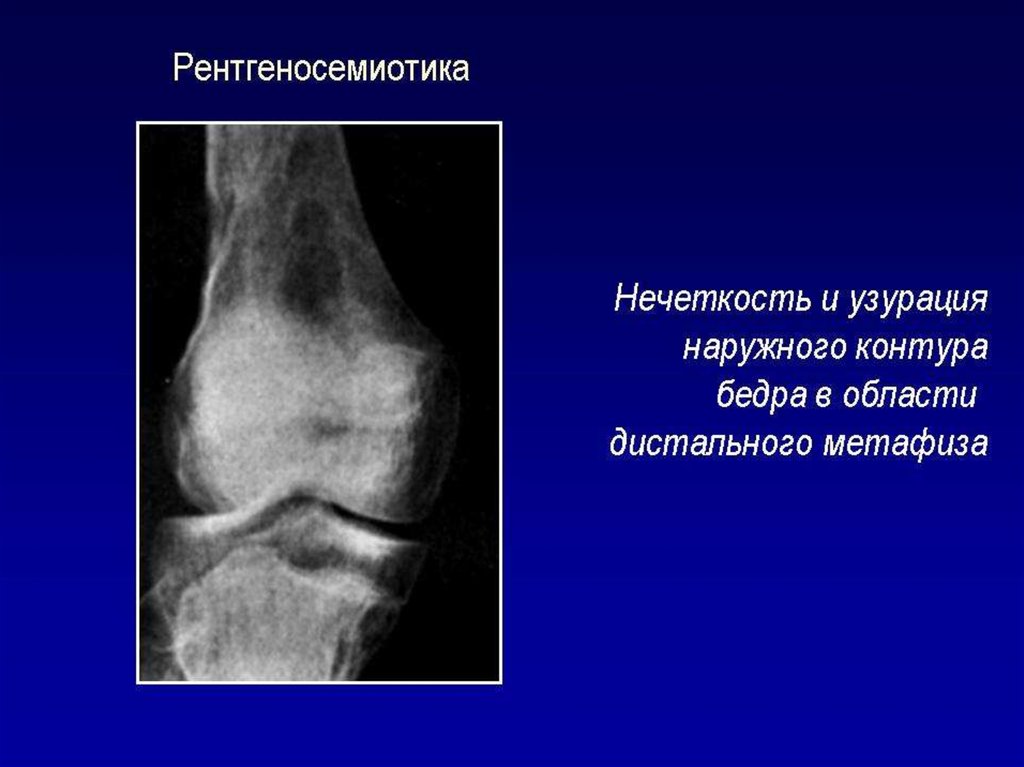

Лучевое исследование костно-суставной системы. Методы исследования. Семиотика